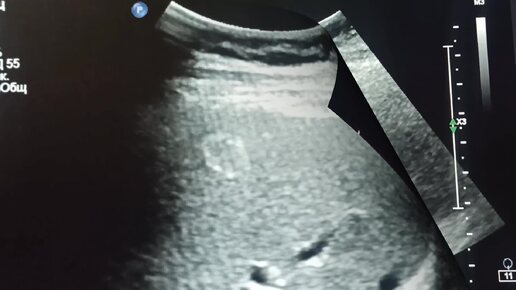

УЗИ для начинающих врачей: Гемангиома (?) правой доли печени